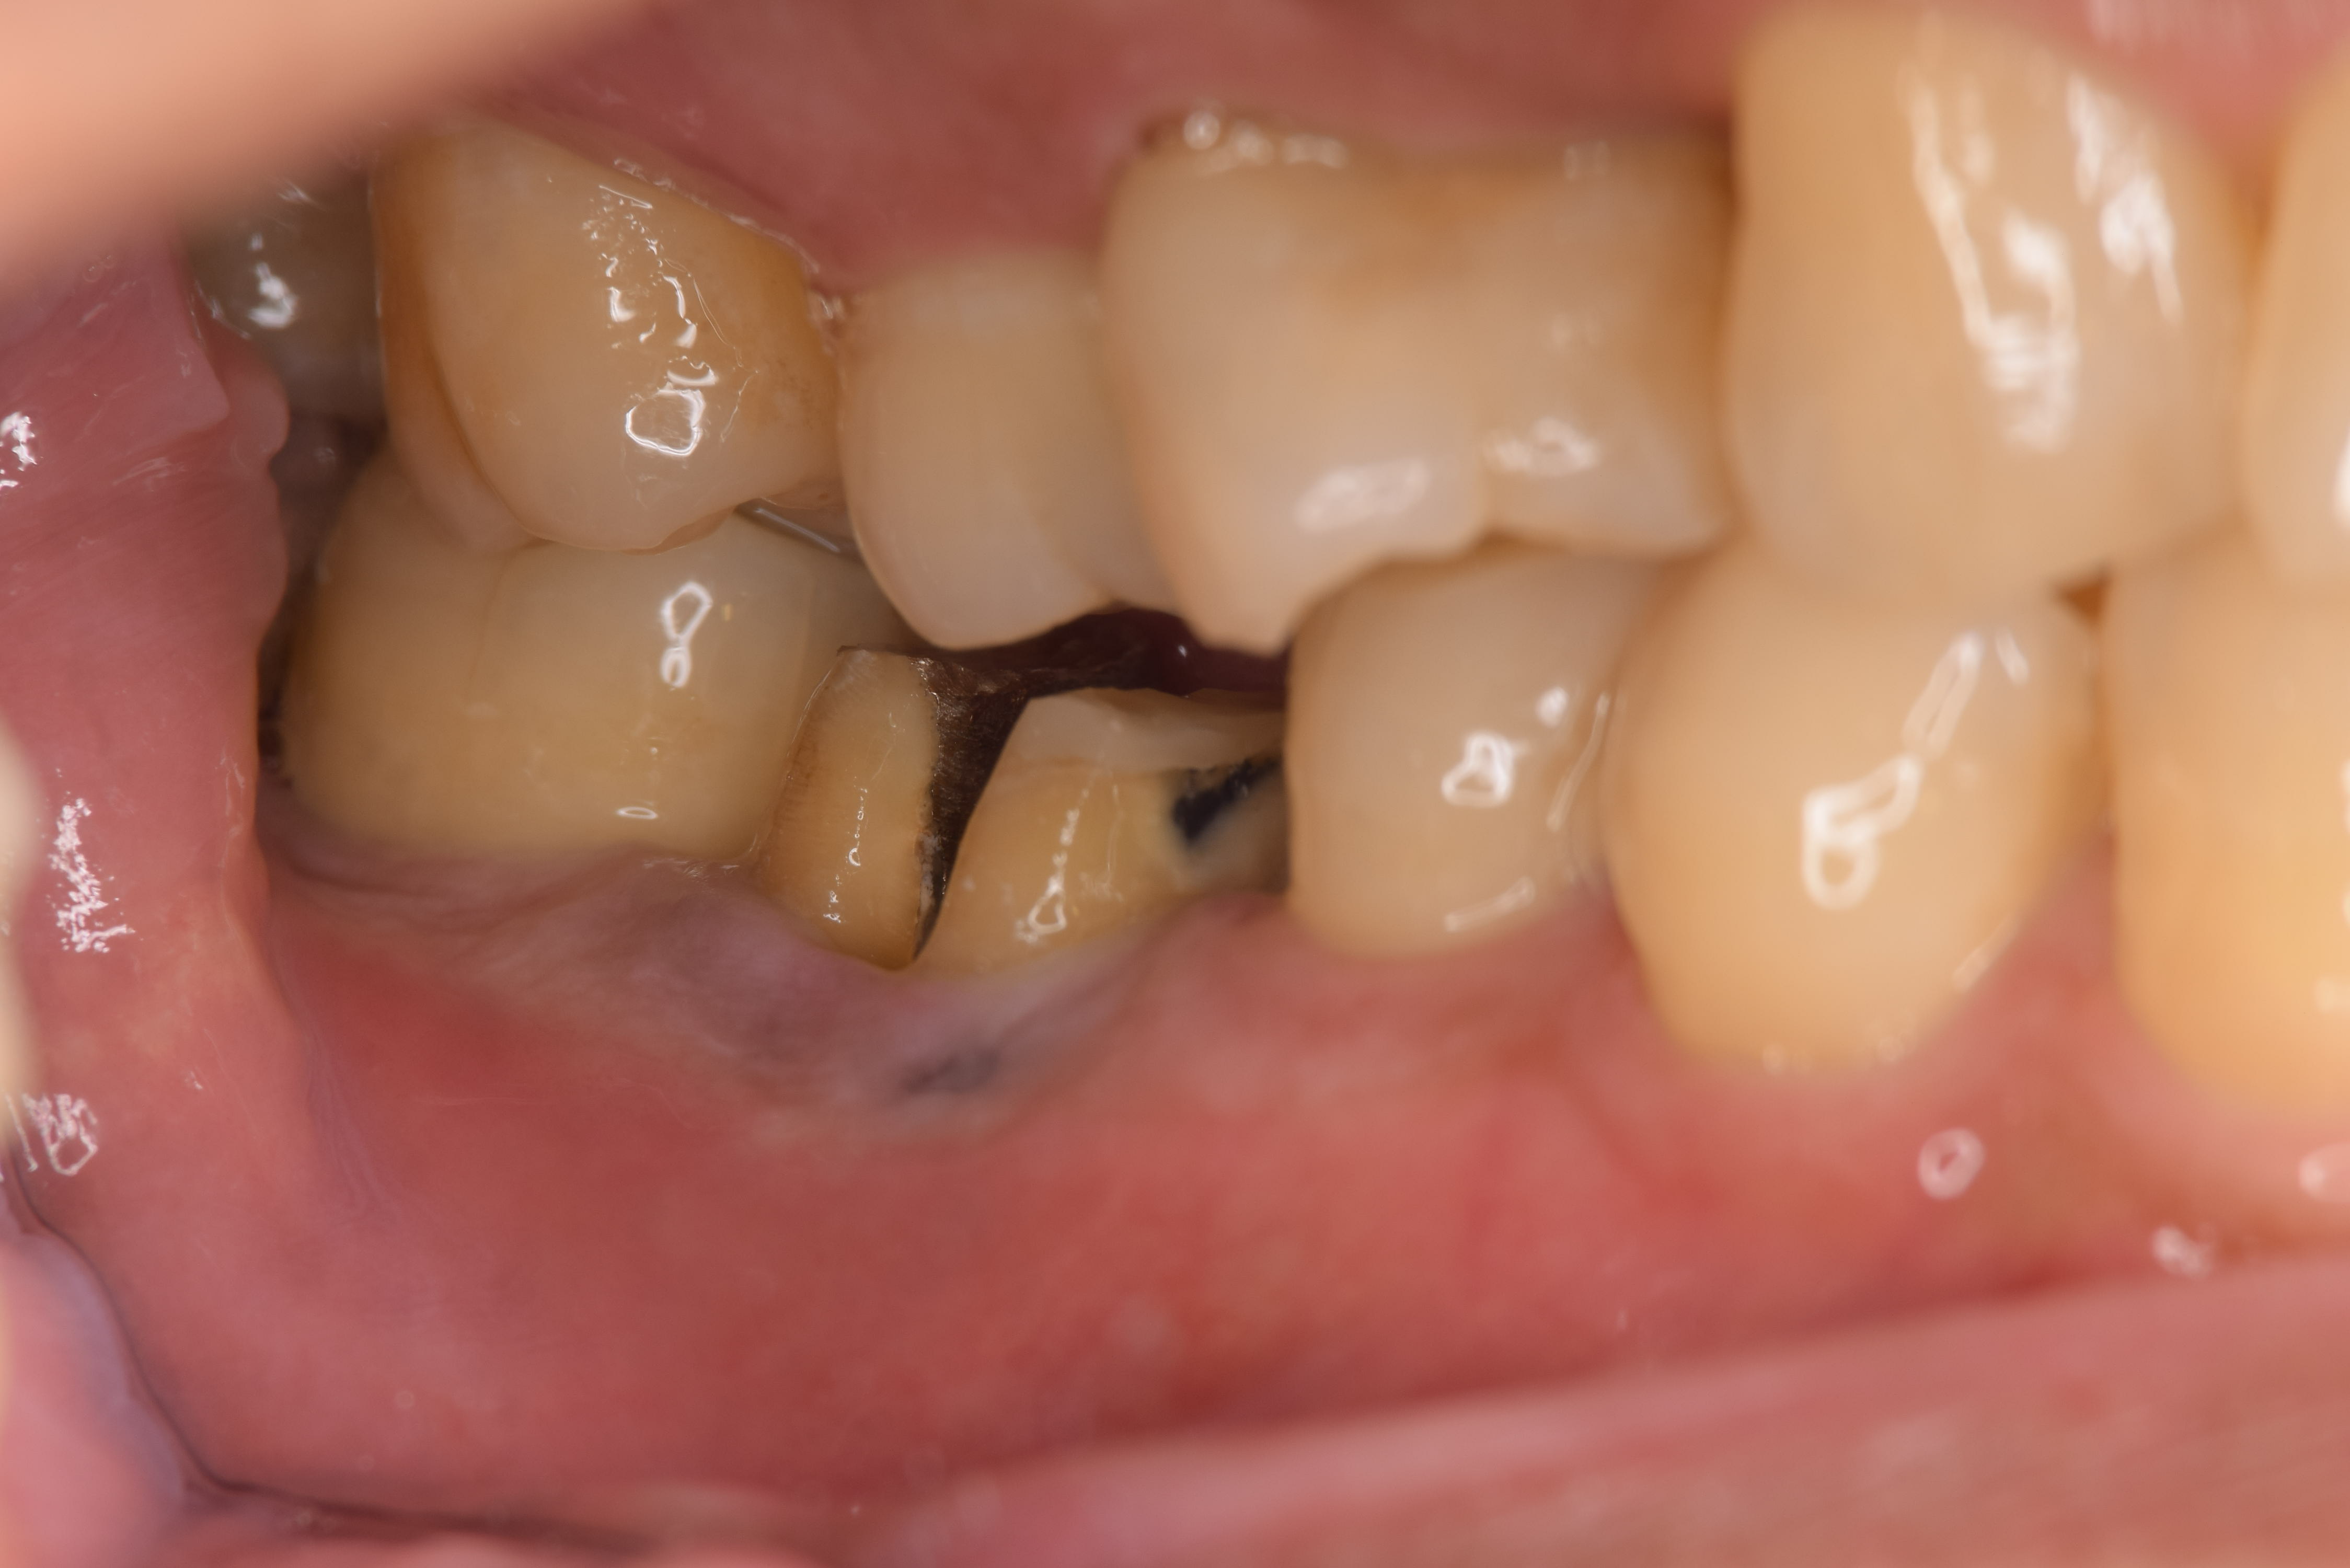

術前の状態です。小さな膿の袋があります。(ミラー像)